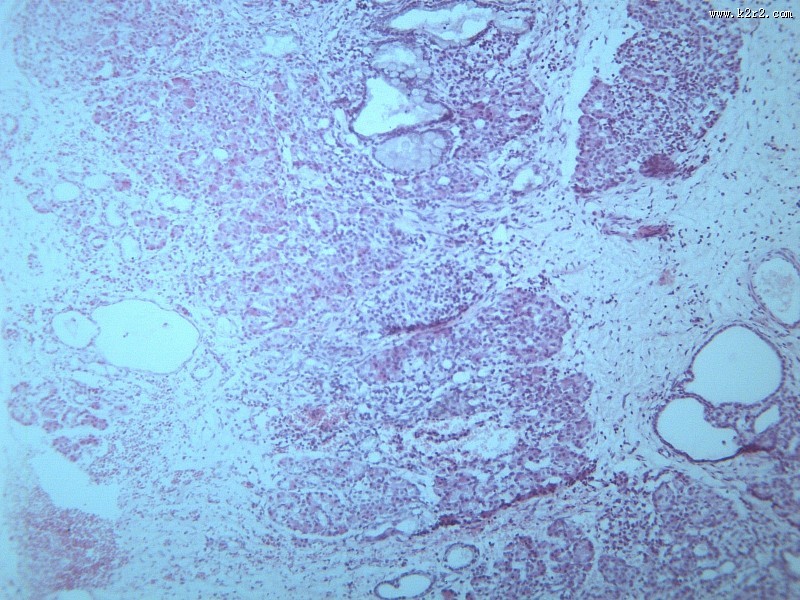

首页 > 其他类别 > 畸胎瘤(12张) > 畸胎瘤 第1张

畸胎瘤 - 第1张